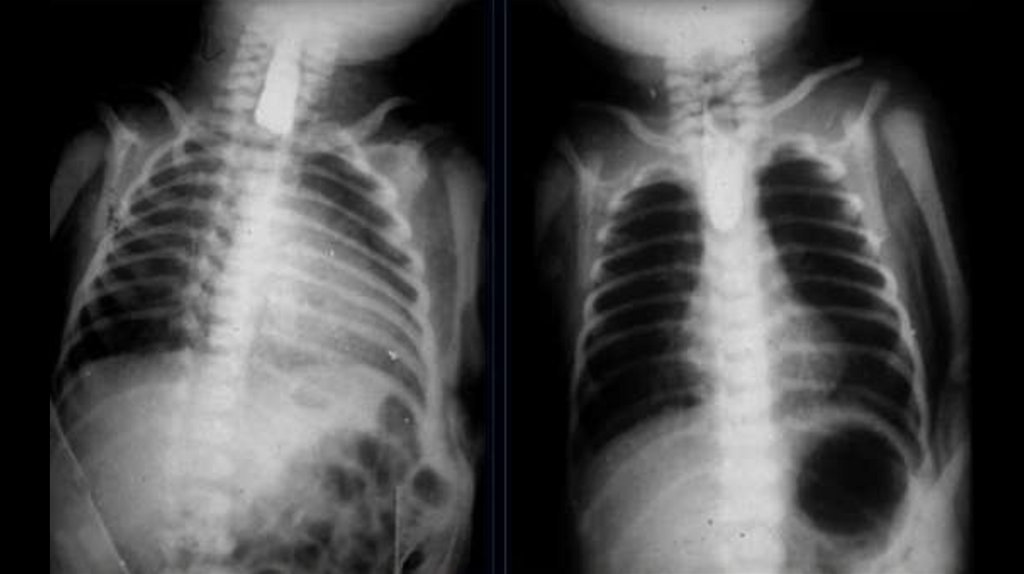

• Атрезия пищевода —

врождённый порок

внутриутробного

развития, при

котором пищевод не

сообщается с желудком.

• Атрезия пищевода

проявляется

слюнотечением, пеной из

носа или рта,

затруднением глотания,

рвотой, синюшностью

кожи и нарушениями

дыхания.

38.